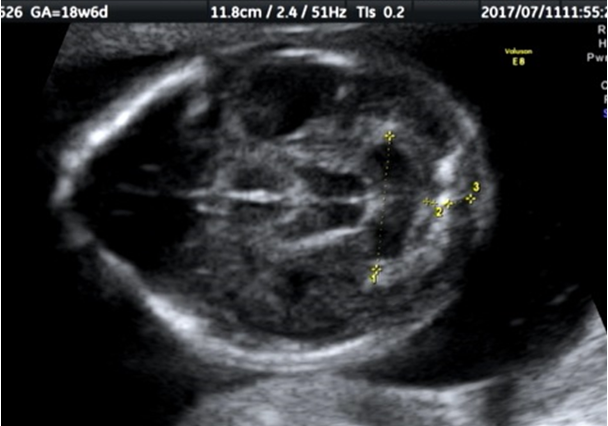

そして、バナナサインは、赤ちゃんの小脳が脊椎の方に落ち込んで、形がバナナのように見えるようになるので、その名前がつけられました。少し無理があるようにも思いますが。

お腹の中の赤ちゃんに、レモンサインとバナナサインがないかを確かめて、もしも疑われた場合には、しっかりと出生前診断のできる施設で再確認する。そのような体制を全国で構築します。